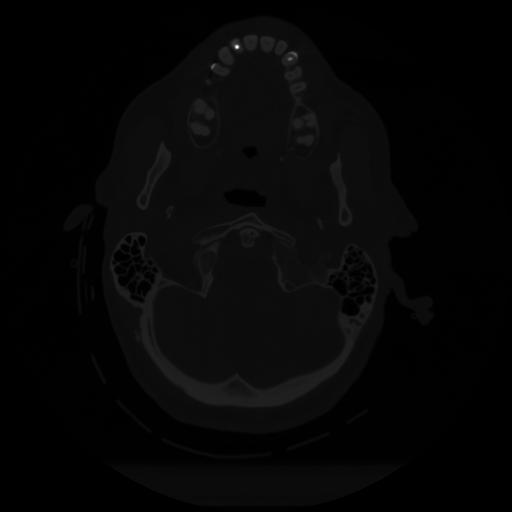

12 P.BLANDAS,,Vol,0.5,P.BLANDAS,,